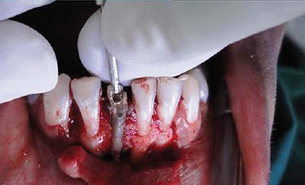

诊断为41牙慢性根尖周脓肿。首先取出41牙根管内尖锐物体,其次完善根管治疗,进行根尖手术,控制根尖周炎症。

病例中患者幼时受到外伤后未及时诊治,而且在疼痛时往根管内放置尖锐物体,进而导致严重的根尖周炎症。由于根管内的异物能够通过疏通取出,故而未利用超声系统。患牙根尖孔尚未愈合,根管粗大,整个治疗过程中要尽量保存剩余牙体组织,修复时也选择与牙本质弹性模量相近的纤维桩进行修复。